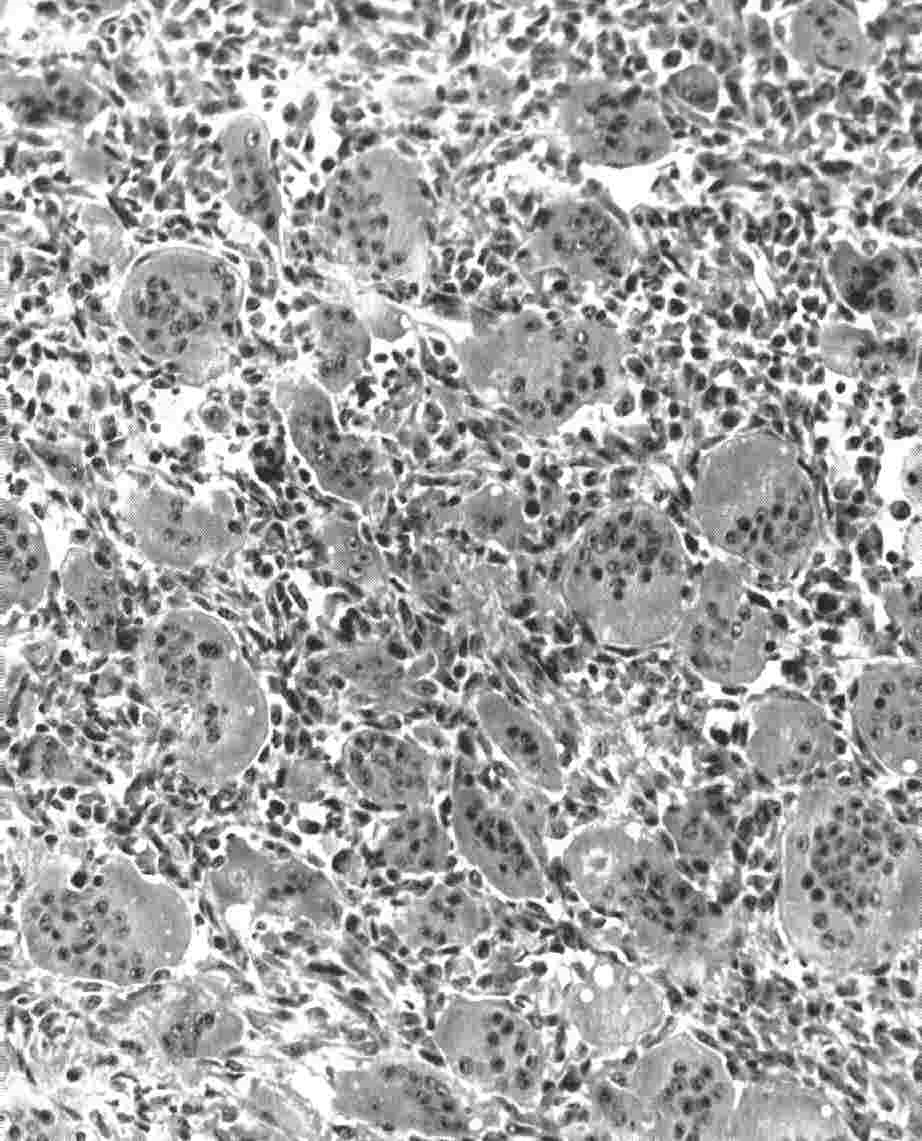

The tumor is reddish in appearance, and comes away in pieces, and may have a poorly defined edge if it’s an aggressive tumour. The basic cell is the giant cell, which has a round/oval shaped nucleus. This multinucleated cell is set in a background of spindle shaped stromal cells, with numerous mitotic figures, and very little intercellular tissue. These giant cells are thought to related to osteoclasts, as they possess all the characteristics of osteoclasts. This contrasts to the giant cells in other lesions, which don’t. This may account for the resorption of bone.

Sheets of multinucleated giant cells can be seen